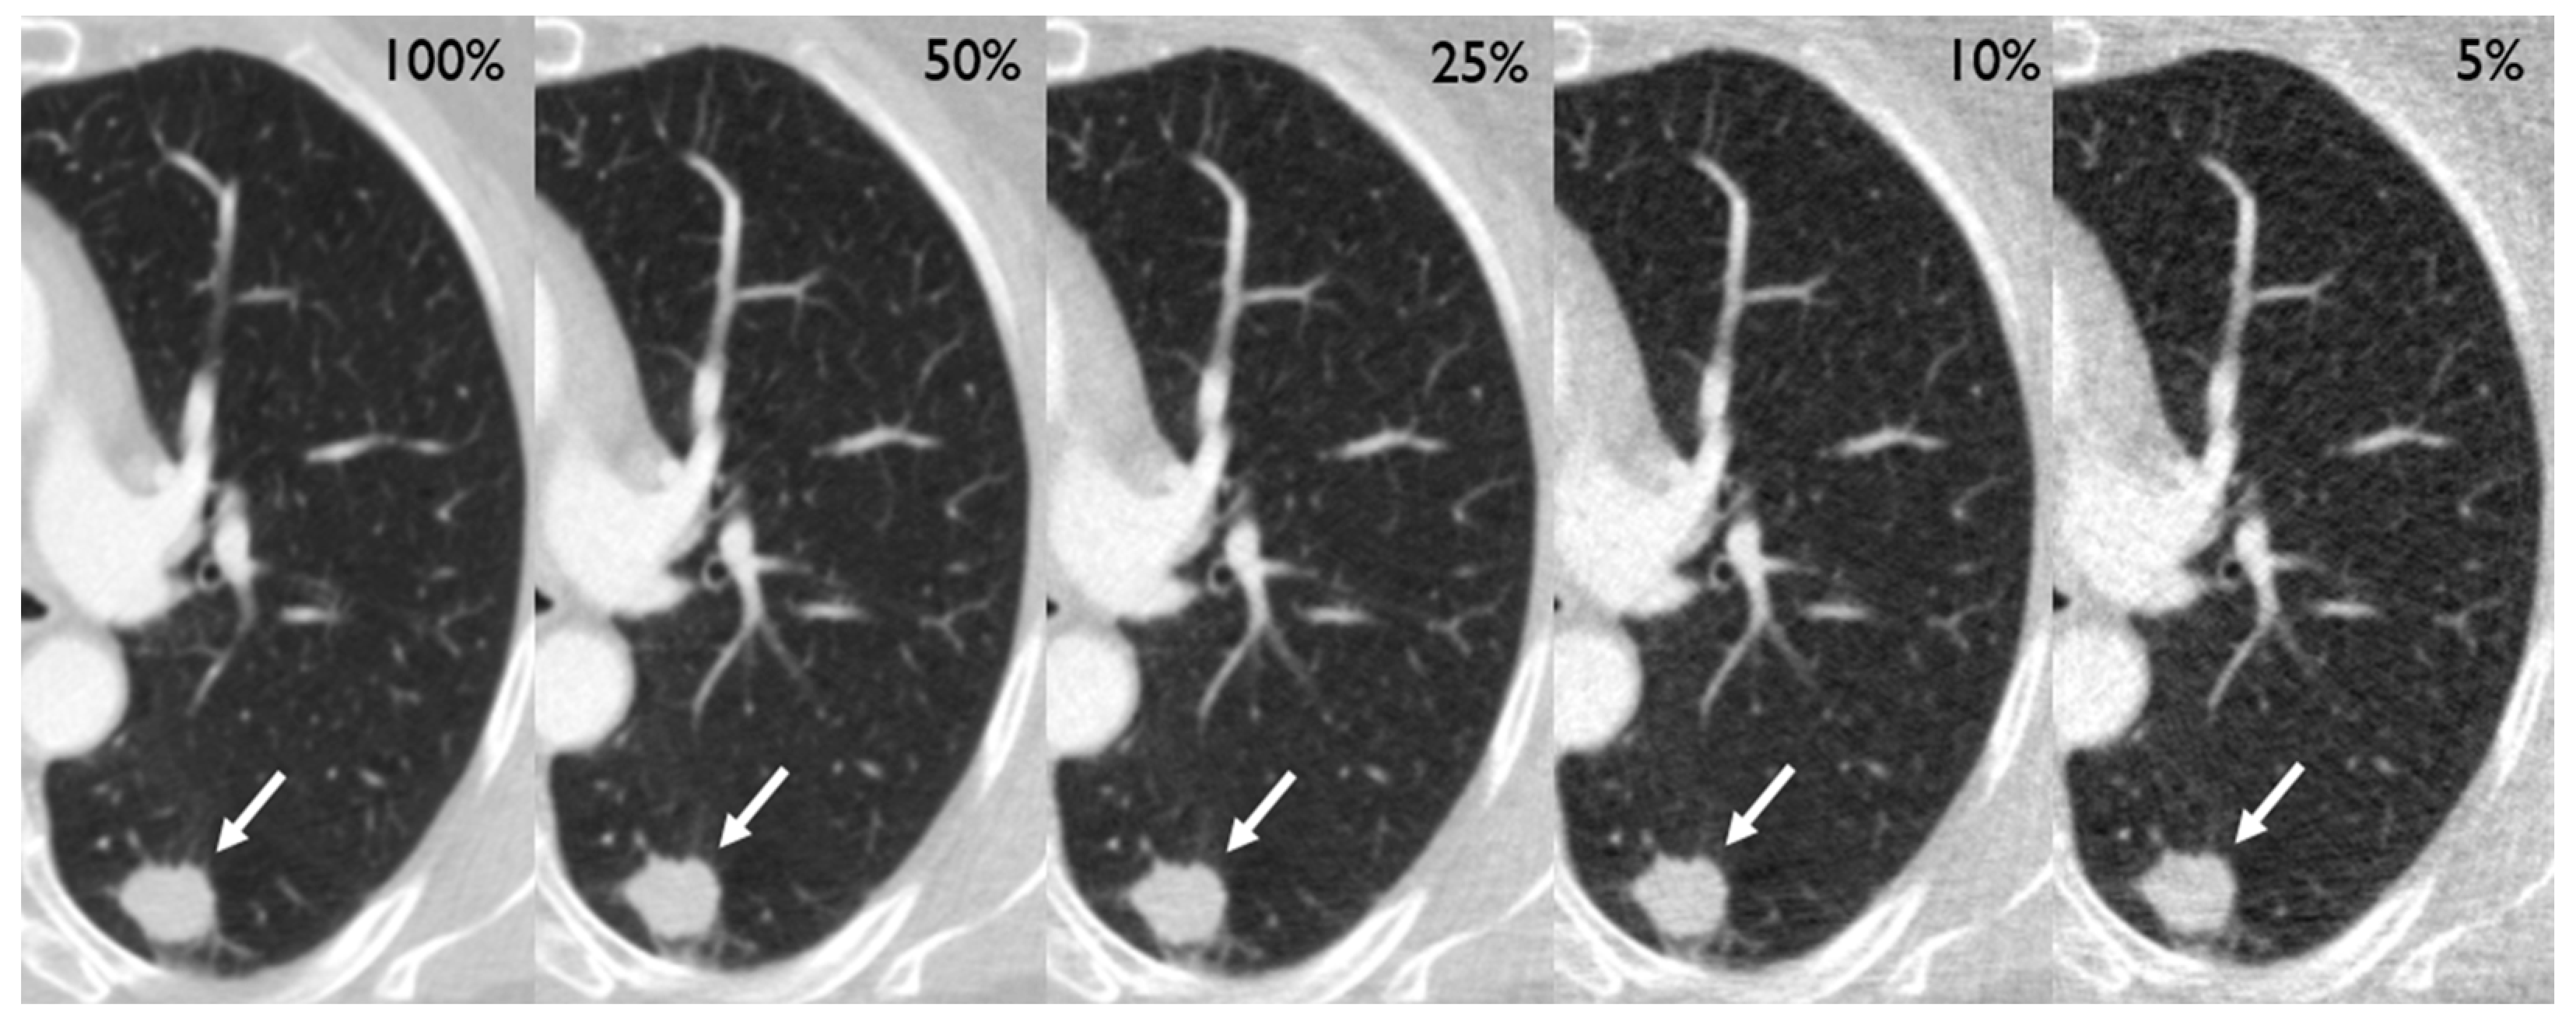

After preparation of the simulations, the CT scans of 210 patients (mean age [SD] 64.5 [9.2] years, 87 females [41%]) containing 250 tumors of the lung (201 solid, 28 part-solid, and 21 ground glass) could be included in the analysis (Table 1). Two exemplary cases are depicted in Figure 2 and Figure 3. Eight patients had to be excluded due to technical reasons, such as incomplete coverage of the lungs.

Figure 2.

Different dose level simulations depicting a 19 mm primary adenocarcinoma in the left lower lobe of a 71-year old female (white arrow), who had initially presented with a cough.

Figure 3.

Different dose level simulations depicting a 14 mm ground-glass nodule in the left upper lobe of a 75-year old female (white arrow) with left-sided chest pain. The lesion turned out to be a primary pulmonary adenocarcinoma.